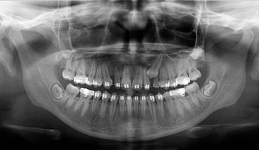

Jedná se o nejnovějším přístroj ze skupiny dentálních hybridních CBCT (3D) + 2D (pan i ceph) systémů. Přístroj umožňuje na základě jediného snímkování vytvořit všechny typy RTG zobrazení, které jsou pro lékaře potřebné.

Používaná technologii tzv. „kuželového paprsku“ a speciální senzory pro minimální zátěž při snímkování pacienta

(o více jak 80% nižší dávka proti klasickému CT).

Pomocí tohoto přístroje je možné zjisti skutečnou situaci v čelistních kostech pacienta tedy množství kosti - můžeme změřit skutečnou šířku i výšku kosti, i kvalitu kosti (hustotu) v místě uvažované implantace. 3D (tříprostorové) zobrazení umožňuje

zvýšit prostorovou představu operatéra ještě před vlastní operací a zároveň pacientovi lépe objasnit a ukázat oblast plánovaného zavedení implantátu.

Pacient „neumí číst“ RTG snímky, ale díky 3D zobrazení vidí „svoji skutečnou čelist“ – např. jak je nízká či úzká, vidí průběh nervu nebo velikost čelistní dutiny, což mu umožní i pochopení nutnosti v některých případech provést pomocné zákroky

ještě před vlastním zavedením implantátu (více - Augmentace - kostní štěp, sinus lift, kostní granulát...).